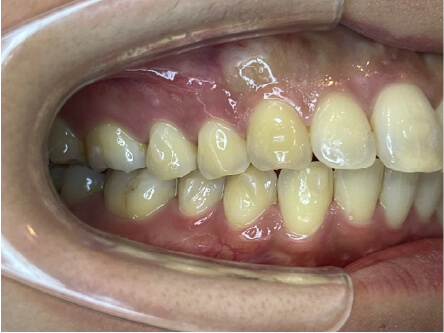

叢生の症例

41歳

/

女性

相談内容

横から見た時のガタガタが気になる

カウンセリング・診断結果

インビザライン、正中は上11に合わせていく、抜歯・拡大装置・IPR・アタッチメントOK

治療内容・方法

アライナー矯正

術後の経過・現在の様子

クリアライナー使用

治療のリスク

痛み・歯根吸収・歯肉退縮・虫歯・後戻り

費用・治療期間

880,000円、7ヶ月

トレーニングなど